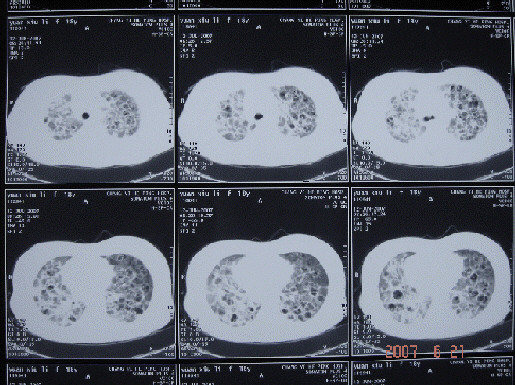

2007年6月ct部分层面

考虑嗜酸性肉芽肿可能性大

嗜酸性肉芽肿早期有肺泡内细胞浸润,中期肉牙肿形成,晚期纤维化和囊肿的形成

2、嗜酸性肉芽肿的结节和囊变以两肺中上肺为主,肋隔角区相对正常,这点与肺淋巴管肌瘤病不同,肺淋巴管肌瘤病的特点是弥漫分布,早期就有囊变,所以我认为可能性不大

狼疮性肺炎病理表现包括畸形肺泡炎、肺泡出血、肺泡壁坏死、水肿、透明膜变、间质纤维化、间质性肺炎、血管炎、血管内膜增生、胸膜和胸膜渗出。sle影像表现无特异性,诊断必须密切结合临床。